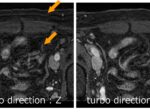

上腹部の脂肪抑制T2WIを撮像する際、CHESS,SPIR,SPAIRなど周波数選択的脂肪抑制法を使用されているご施設が多いのではないでしょうか?当院もそうです。しかし、これらは磁場の不均一に弱いという特徴があります。皮下脂肪の厚みがある患者さんを撮像していると、たまにFig.1のように脂肪抑制不良を経験します。対策としては、ボリュームシムの範囲を変更したり、F0をマニュアルで合わせたりしますが、それでも上手くいかず、ドツボにはまることもあります。

そこで、この撮像時間の問題を解決するために、今回はSingle Shotでの撮像を取り入れました。今までDIXON法をSingle shotで撮像したことはありませんでしたが、撮像してみるとブラーリングは多少気にはなるものの、20秒の息止め1回で撮像できるので、何度も撮り直すよりも有用だと思います(Fig.2)。一つ注意点としては、Philipsの場合、Single Shotでの撮像はScan modeがM2D(シーケンシャル法)に設定されているため、MS(マルチスライス法)に設定を変更する必要がある点です。私は最初ここでつまずきました。